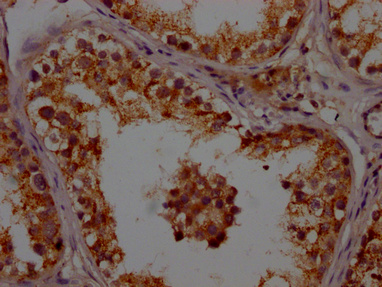

• IHC image of CSB-PA001948LA01HU diluted at 1:200 and staining in paraffin-embedded human testis tissue performed on a Leica BondTM system. After dewaxing and hydration, antigen retrieval was mediated by high pressure in a citrate buffer (pH 6.0). Section was blocked with 10% normal goat serum 30min at RT. Then primary antibody (1% BSA) was incubated at 4°C overnight. The primary is detected by a Goat anti-rabbit polymer IgG labeled by HRP and visualized using 0.05% DAB.